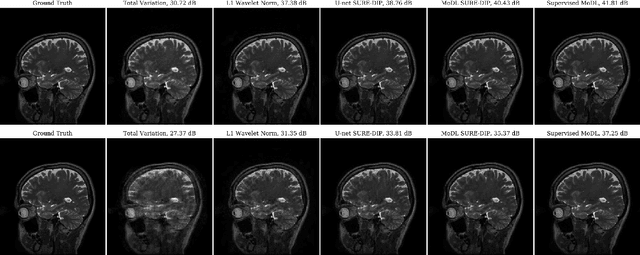

Abstract:Deep learning algorithms that rely on extensive training data are revolutionizing image recovery from ill-posed measurements. Training data is scarce in many imaging applications, including ultra-high-resolution imaging. The deep image prior (DIP) algorithm was introduced for single-shot image recovery, completely eliminating the need for training data. A challenge with this scheme is the need for early stopping to minimize the overfitting of the CNN parameters to the noise in the measurements. We introduce a generalized Stein's unbiased risk estimate (GSURE) loss metric to minimize the overfitting. Our experiments show that the SURE-DIP approach minimizes the overfitting issues, thus offering significantly improved performance over classical DIP schemes. We also use the SURE-DIP approach with model-based unrolling architectures, which offers improved performance over direct inversion schemes.